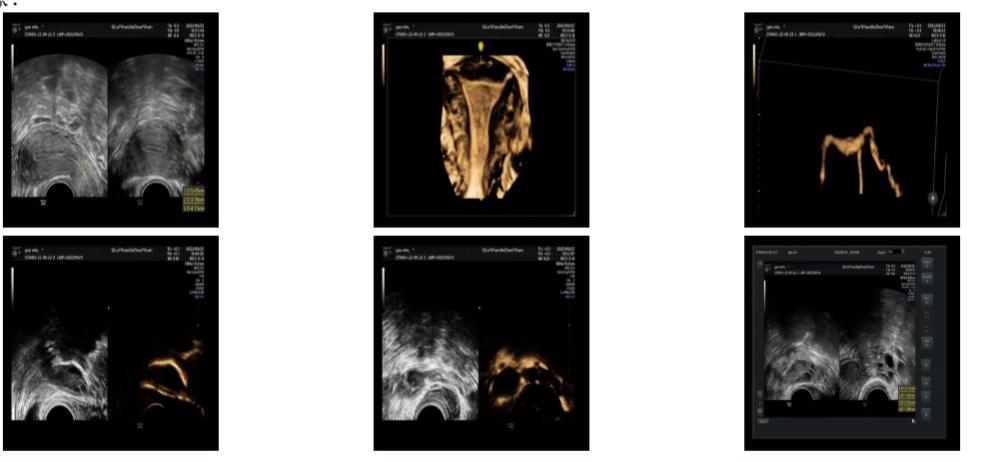

小敏夫妇担心X线有辐射,并且害怕会有疼痛,李晓露向其讲解了子宫输卵管造影的过程、“X线下子宫输卵管造影”和“子宫输卵管四维超声造影”的区别,小敏夫妇商量后选择了后者。2022年9月,在充分的心理疏导后,李晓露为患者小敏进行了细致的子宫输卵管四维超声检查,同时对输卵管进行了相应的疏通。随后两个月,李红继续为小敏进行促排卵治疗,终于在2022年12月成功妊娠。现在小敏已经怀孕2个多月,各项指标稳定,安心孕育着新的生命。

子宫输卵管四维超声造影是将六氟化硫微泡造影剂经置入宫腔的导管注入宫腔,含微小气泡的造影剂可以通过两侧宫角弥散至输卵管。通过四维超声成像,实时、连续、动态观察宫腔形态、输卵管走形以及盆腔弥散情况,从而评估输卵管通畅性以及观察宫腔、盆腔等病变。

(1) 操作过程简便,图像清晰,可实时动态显示子宫、输卵管、盆腔的情况;

(2) 整个检查过程无放射性,安全性高,造影两周后可备孕;

(3) 微泡造影剂释放时对输卵管粘连有一定疏通作用,造影剂代谢快,过敏反应发生率极低;

(4) 可静态或动态存储图像用于后期分析,减少患者的检查时间。